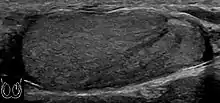

The incidence of infertility is decreased if surgical orchiopexy is carried out before the 1–3 years but the risk of malignancy does not change. Because of the superficial location of the inguinal canal in children, sonography of undescended testes should be performed with a high frequency transducer. At ultrasound, the undescended testis usually appears small, less echogenic than the contralateral normal testis and usually located in the inguinal region [Fig. 29]. With color Doppler, the vascularity of the undescended testis is poor.

![Fig. 29. Undescended testis. (a) Normal testis in the scrotum. (b) Atrophic and decreased echogenicity of the contralateral testis of the same patient seen in the inguinal region.[citation needed]](../I/Scrotal_ultrasonography_of_undescended_testis.jpg.webp) Fig. 29. Undescended testis. (a) Normal testis in the scrotum. (b) Atrophic and decreased echogenicity of the contralateral testis of the same patient seen in the inguinal region.

Fig. 29. Undescended testis. (a) Normal testis in the scrotum. (b) Atrophic and decreased echogenicity of the contralateral testis of the same patient seen in the inguinal region.